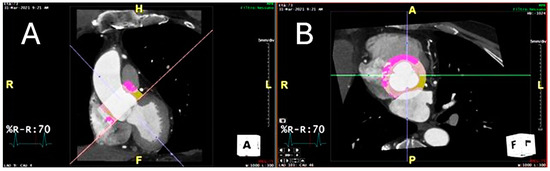

2.4. Technical Steps Required to Measure Perivascular Adipose Tissue Attenuation of the Proximal Ascending Thoracic Aorta on Chest Computed Tomography Angiograms